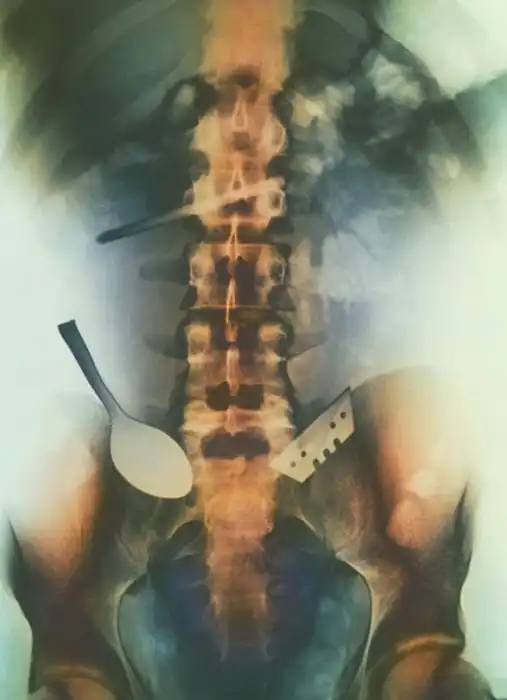

Порой даже не верится, с какими странными и необычными повреждениями в травматологию могут поступить пострадавшие. Всю эпичность профессии врачей травматологии могут с легкостью подтвердить рентгеновские снимки.